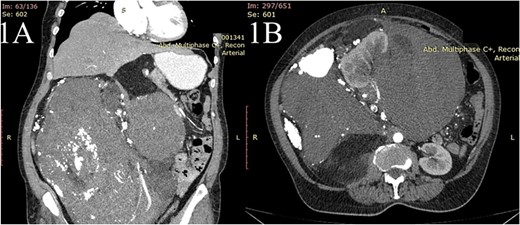

A 63-year-old woman presented with a 6-month history of progressive weight loss, nausea, vomiting, diffuse abdominal pain and constipation. An ultrasonography exam revealed a huge retroperitoneal mass. The computed tomography with intravenous contrast revealed a large heterogenous mass having multiple linear septation and HU value of −90 of 27 × 29 × 36 cm (Fig. 1A and B) originating from the retroperitoneal space, extending from the sub-hepatic space to the pelvis with a cranial displacement of the liver and a left displacement of the pancreas, stomach and the small bowel and encasement of the right kidney. Fine needle biopsy revealed liposarcoma. The preoperative assessment revealed only mild anemia (Hb = 9.4 mg/dl, erythrocytes—4.7 * 1012/l, hematocrit = 31%).

The contrast-enhanced computed tomography (CT) scan shows (A) a huge mass extending from the sub-hepatic region to the pelvis with the cranial displacement of the liver and (B) the same mass causing encasement the right kidney.